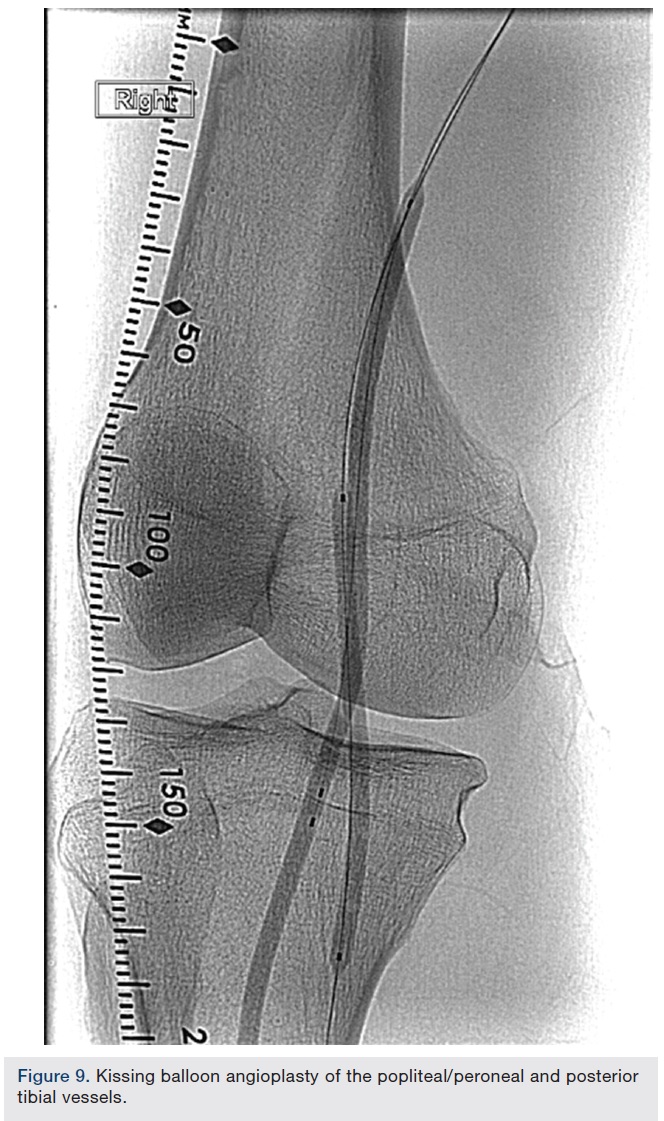

Atherectomy with JETSTREAM. Atherectomy was performed in two stages. During the first stage, we had wire access from the popliteal to the peroneal artery. Before crossing from the posterior tibial, we wanted to treat the popliteal/peroneal segment. A 2.4 mm/3.4 mm JETSTREAM atherectomy device was advanced into the popliteal and activated. The device must be activated with the blades down. A pilot channel will remove some of the plaque. The device is advanced at a rate of no more than 1 mm per second. The operator will need to listen to the pitch of the device. A depressed pitch suggests that the device rotation has slowed down, and the operator should then carefully pull the device back and re-advance. The operator must not allow the aspirational capabilities of the device to be overwhelmed. After successful atherectomy “blades-down,” a “blades-up” run was then performed with the JETSTREAM device (Figure 7). During the second stage of atherectomy, the peroneal and posterior tibial arteries required further therapy. For this stage, we obtained posterior tibial access, crossed the posterior tibial CTO, and snared the posterior tibial wire. We proceeded with the use of a 1.85 mm JETSTREAM device. The tibial device has the rotational capabilities without the “blades-up” feature, and also features active aspiration, like the larger JETSTREAM devices. We were able to atherectomize the posterior tibial and peroneal arteries (Figure 8). Angiographic images post atherectomy demonstrate significant plaque reduction. After atherectomy, we proceeded with kissing balloon angioplasty of the popliteal/peroneal and posterior tibial arteries (Figure 9). Angiography of the popliteal artery post atherectomy showed significant improvement (Figure 10). After removal of the pedal sheath, brisk flow was noted (Figure 11). The procedure was concluded with the resolution of the stenosis from the popliteal artery and restoration of flow in two tibial vessels (Figure 12).